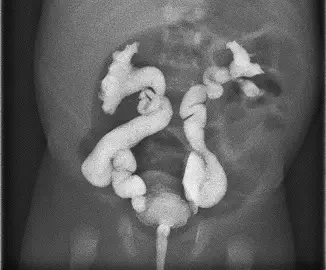

2個月大男嬰因發高燒入院治療,檢查發現泌尿道感染合併菌血症及腦膜炎,經抗生素治療 3 天後發燒逐漸緩解,腎臟超音波發現兩側水腎,遂安排 voiding cystourethrogram ,檢查結果如圖所示,應診斷為: 圖片描述

從 VCUG 影像可見雙側輸尿管及腎盂集合系統注入造影劑後出現:

• 輸尿管明顯擴張,呈蛇行扭曲狀(tortuosity)。

• 腎盂及腎盞嚴重擴張,集合系統內腎乳頭印象消失。

• 造影劑回流範圍深入腎盞並累及腎實質周邊,顯示尿液逆流達最嚴重等級。

上述所見屬於 VUR 分級中最嚴重的一級,符合 grade V 特徵。